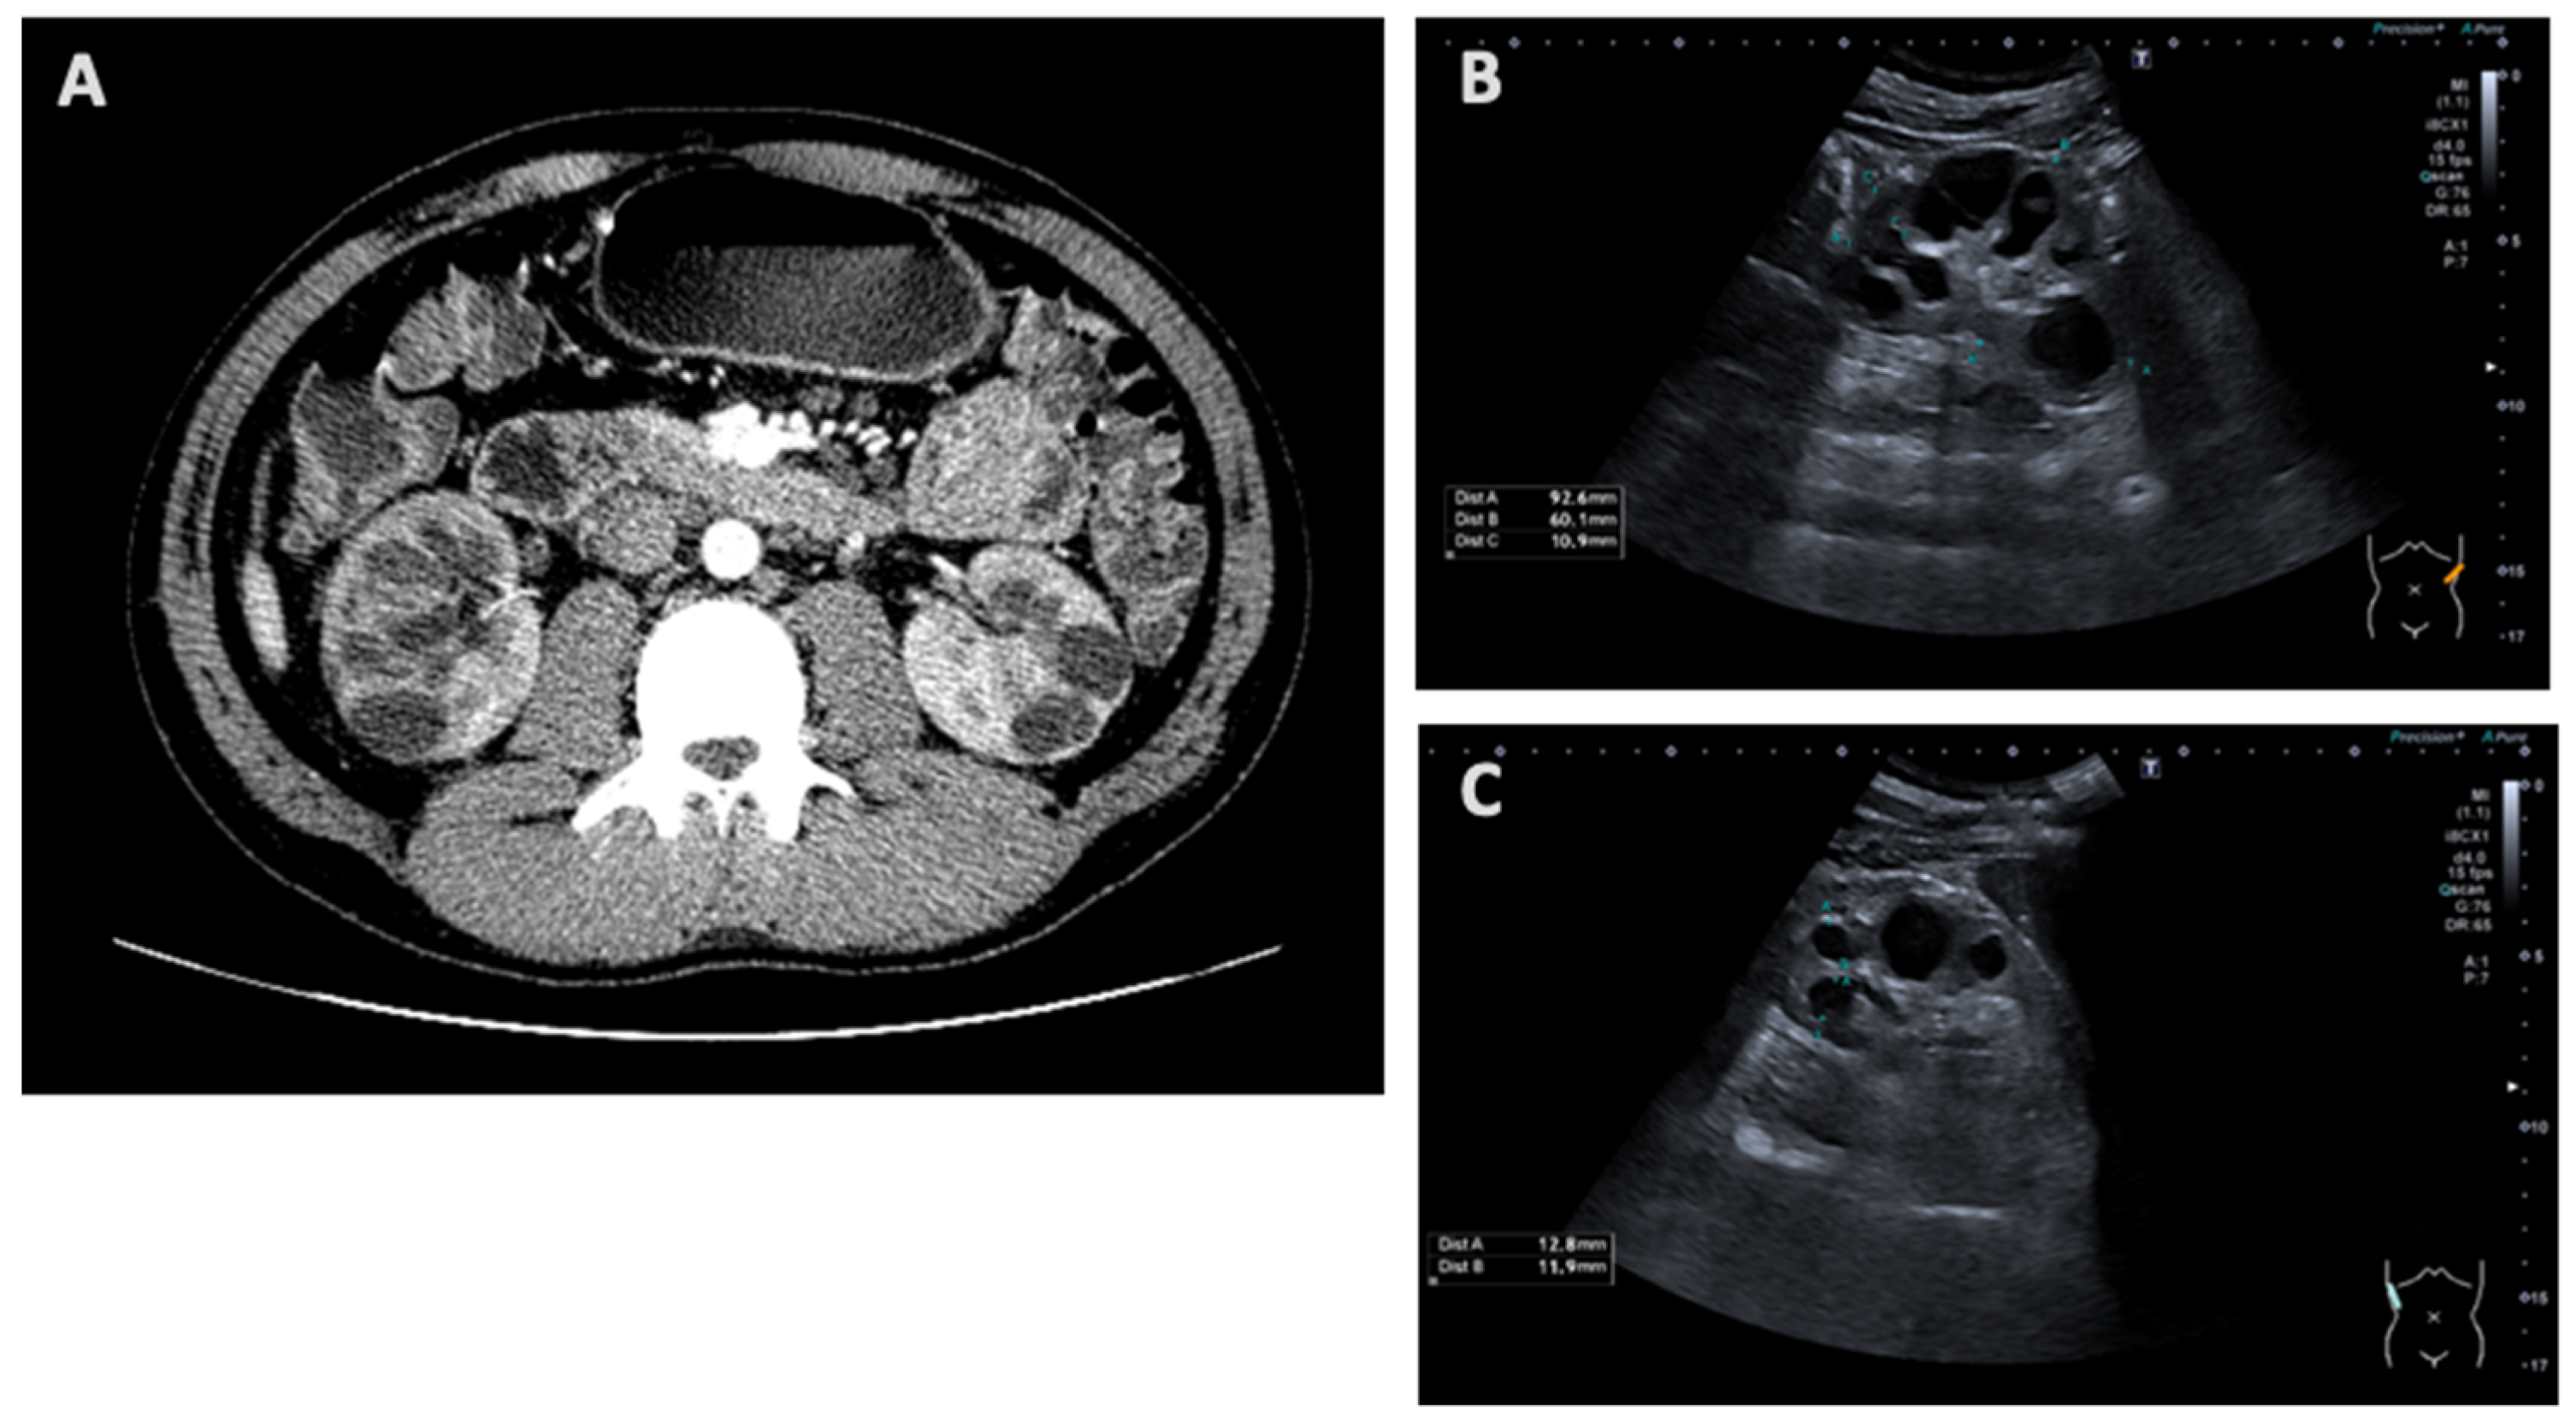

| Kidney imaging | N/A | Bilateral hyperechogenic kidneys | Multicystic dysplastic kidney/polycystic kidney | N/A | Signs of chronic kidney disease, microcalcifications and simple cysts | Increased parenchymal echogenicity |